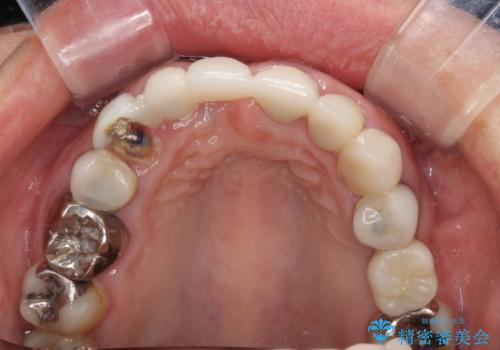

- 前歯が土台ごと外れてしまうとのことで来院された患者様です。

問題の歯は、歯根まで破折している状態で、抜歯が必要と判断されました。

周辺の歯は20年以上前に装着したクラウンで、色合いや形態が気になっているとのことで、オールセラミックブリッジにて補綴治療を行うこととしました。

ところが、土台となる歯は、十分な維持力が得られないほど歯ぐきの中に埋もれており、歯ぐきも腫れやすい状況でした。

まずは土台の歯を引っぱり出し、外科処置により歯肉の状態を十分に整えた上で、オールセラミッククラウンにて補綴することとしました。

元々の土台は歯肉の中に埋もれており、歯肉が著しく腫れている状態だったため、歯を引っぱり出すこととしました。引っぱる期間は2ヶ月ほどで済み、その後歯周外科処置を行ったことで、土台周りの歯肉は腫脹のない健全な状態へと改善されました。